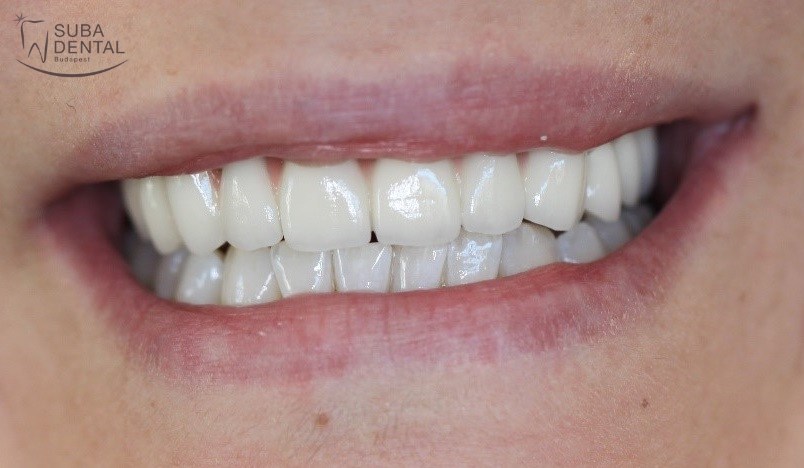

Az koronák végleges ragasztása után páciensünk újra boldogan tud mosolyogni, nem kell többé takargatnia a fogait.

Felhívtuk páciensünk figyelmét a rendszeres ellenőrzések fontosságára, és megmutattuk neki a helyes otthoni tisztítás alapjait.

A kész felső fémkerámia körhíd szájban